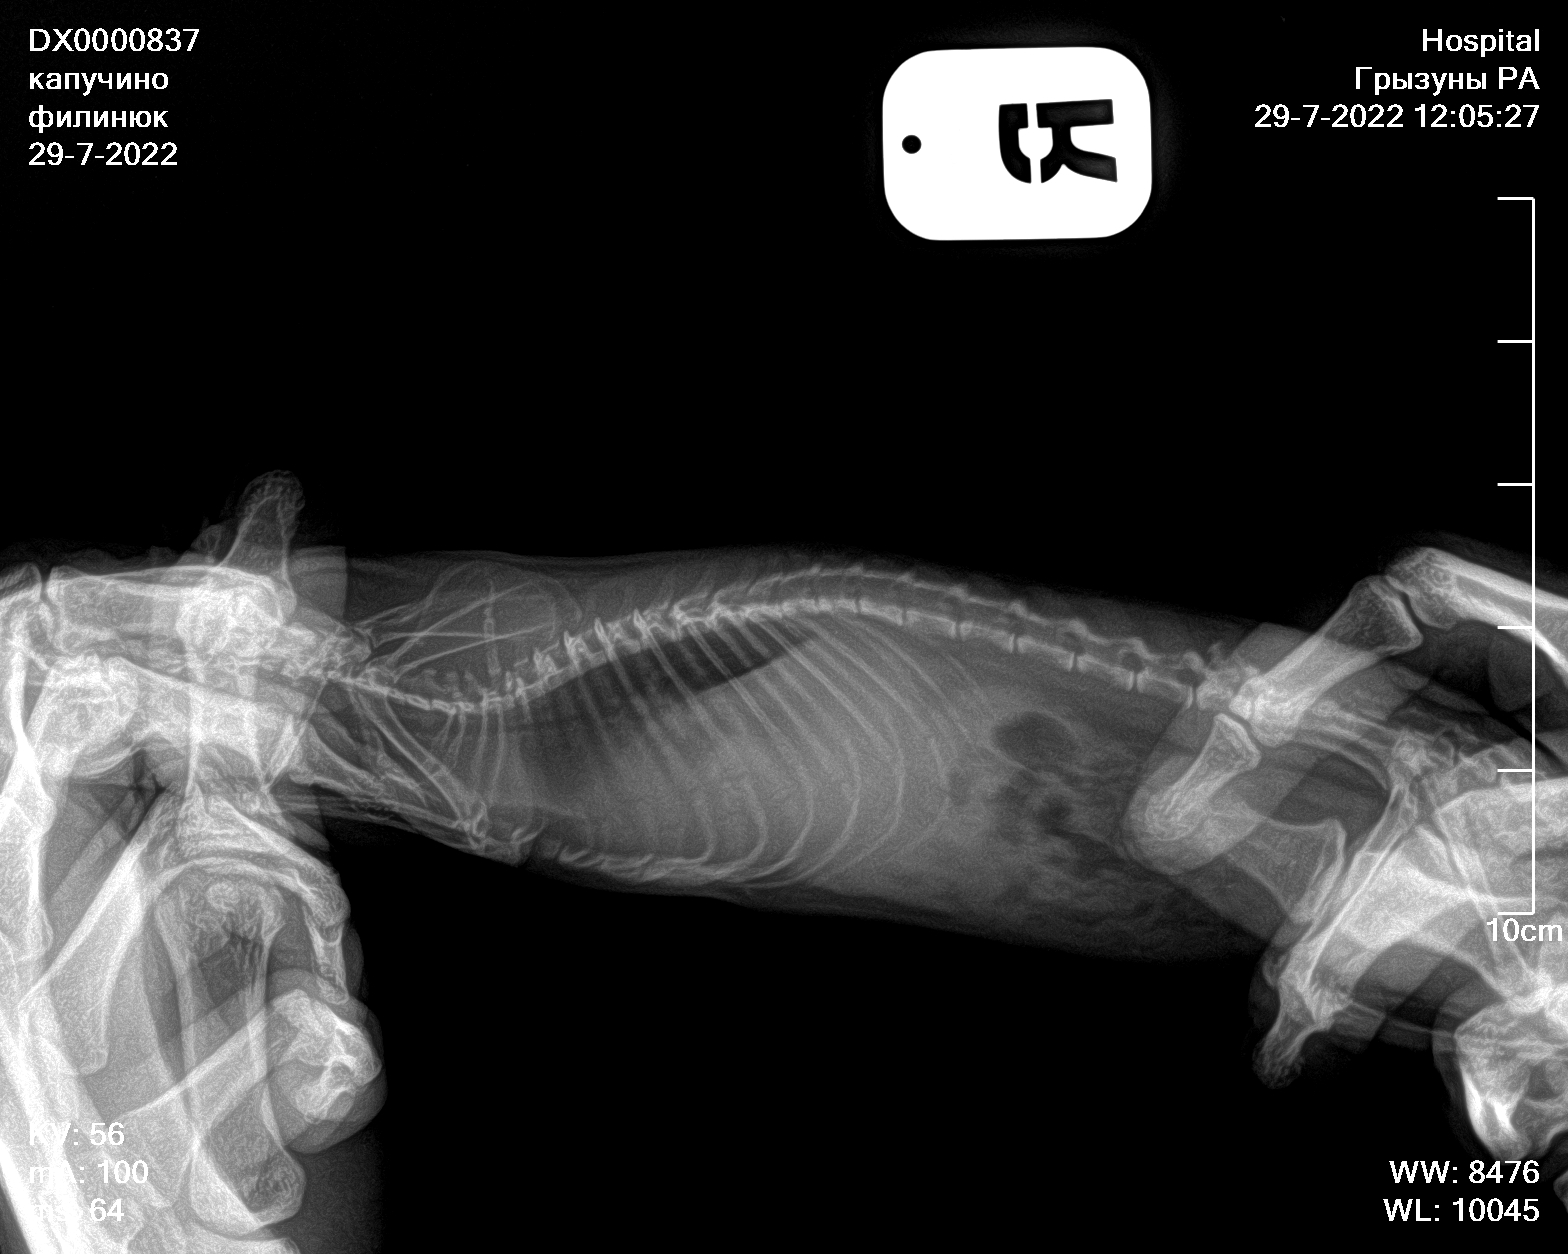

Сделали сегодня рентген новый, посоветовали попробовать продавать 5/5 асд-2 в течении 1-2 месяцев, посмотреть результат

Вложения

3feac979bae970f.jpg

4739d2500821714.jpg

АСД можете подавать, хуже не будет, но и эффекта вероятно не будет. Я когда-то его пробовала давать крысам, никаких результатов небыло, так что в эти сказки больше не верю. Антибиотик обязательно давать, преднизолон и фуросемид тоже.

По рентгену надо консультироваться на других форумах или вконтакте, где раньше консультировались, тут я никак не помогу, увы.